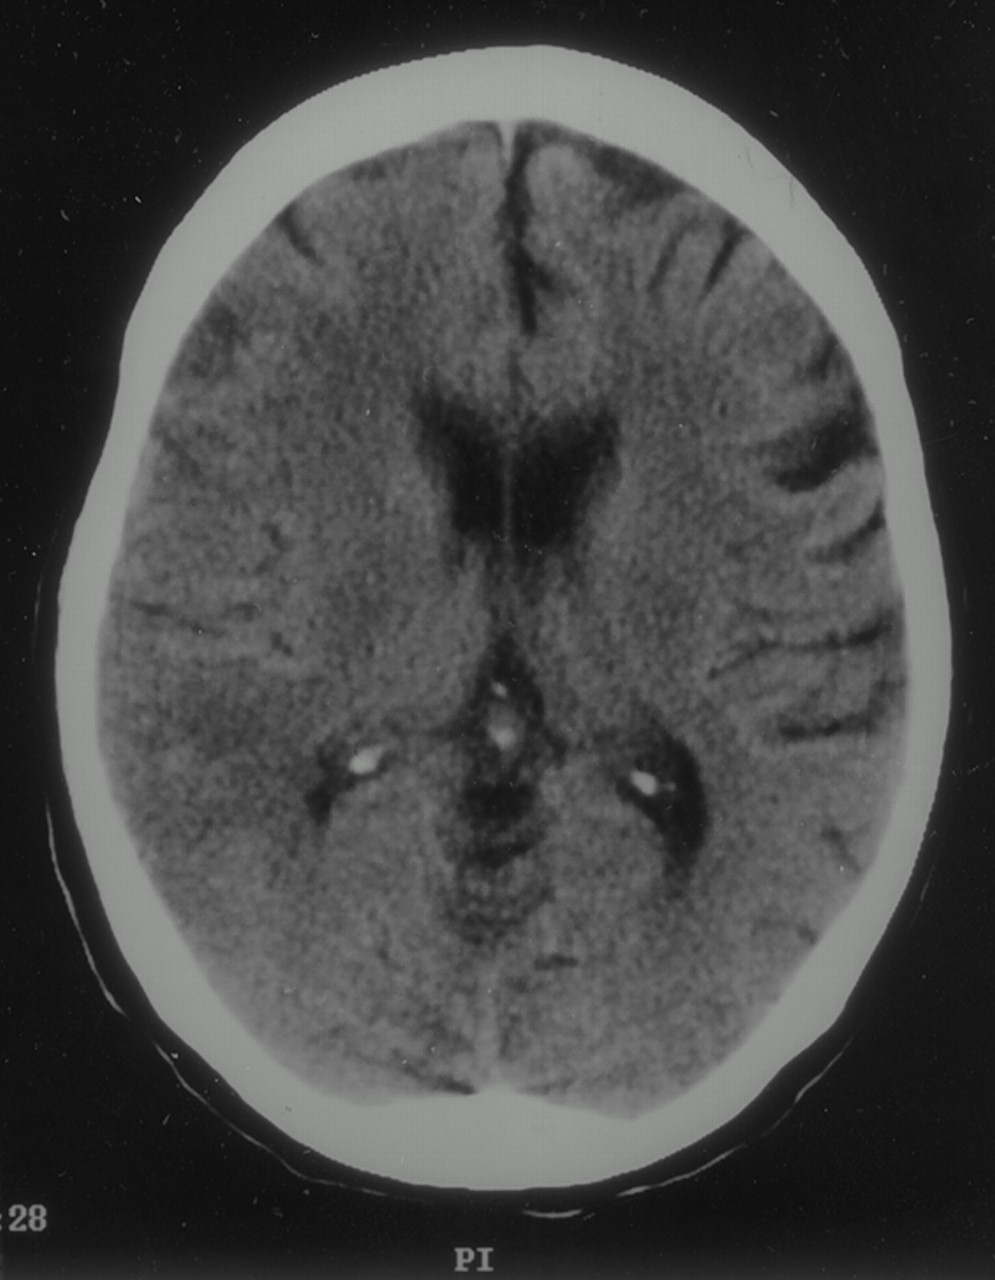

一位80岁的老妇人出现进行性吞咽困难的历史,最初为液体,固体食物,后来和严重的体重在过去的6个月。她正在卡托普利对高血压。初步调查显示食管恶性狭窄的存在。她接受了选修软式内镜下有意识的镇静,证实了恶性狭窄esophagogastric结,连同一个小esophagotracheal瘘。多个小活检是,证实食管癌的存在。她的意识水平恶化后立即手术。她变得反应迟钝,但仍血液流动稳定。检查发现左轻偏瘫的脸,胳膊,腿,弯曲右上肢疼痛的反应。头部的一个紧急unenhanced CT扫描显示右半脑实质的空气(图)。右侧沟被抹去,提示急性大脑中动脉梗塞。被诊断为脑空气栓塞。她是保守治疗,100%的氧气治疗。经胸廓的超声心动图与泡沫的对比显示,没有证据表明从右到左的心脏内的分流。她出院了处于植物人状态2周后入学。

神经系统表现是无数,包括改变意识,癫痫发作,和焦赤字。CT扫描是有价值的在这个如果进行早期检测,IV空气迅速吸收和延迟会导致诊断的失败。中枢神经系统功能障碍的结果机械小动脉的阻塞,导致脑缺血和air-injured上皮的thrombotic-inflammatory响应。这导致一个短暂的脑血流量下降和神经功能。治疗应该开始就有一种强烈的临床怀疑诊断,包括去除空气源,100%的氧气面罩,高压氧。这种治疗的目的是快速减少的体积空气栓子。最近的实验数据表明,代理与抗凝和抗炎作用可能的潜在好处在受试者的风险给予预防性脑空气栓塞。5、6⇓